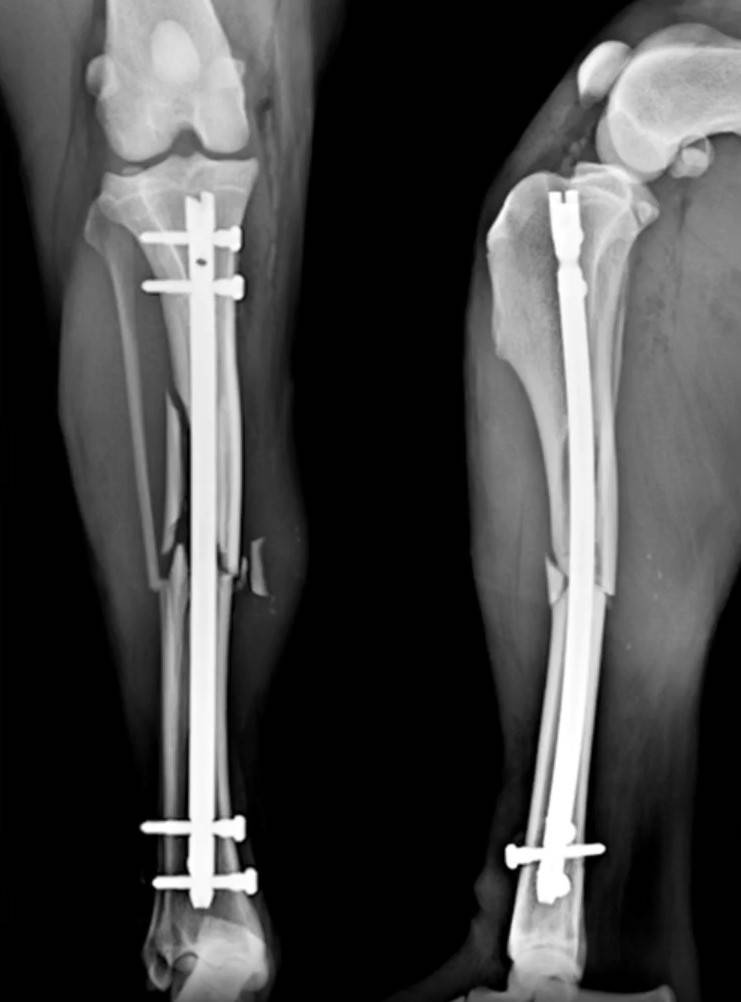

Surg'X Interlocking Nail Fracture Fixation Lab

Surg'X Interlocking Nail Fracture Fixation

• Veterinary Interlocking Nail (ILN) fracture fixation concepts, biomechanics and evolution of ILN fracture fixation

• Surg'X ILN system presentation, technical features, indications and clinical evaluation.  for surgical management of long-bone fractures

• Pre-operative surgical planning and various approaches using ILN systems

• Step-by-step instructions on surgical technique review, hands-on dry bone application and hands-on wet lab application

• To understand the biomechanical principles of Interlocking Nail (ILN) fracture fixation

• To understand indications for ILN in the surgical management of long-bone fractures